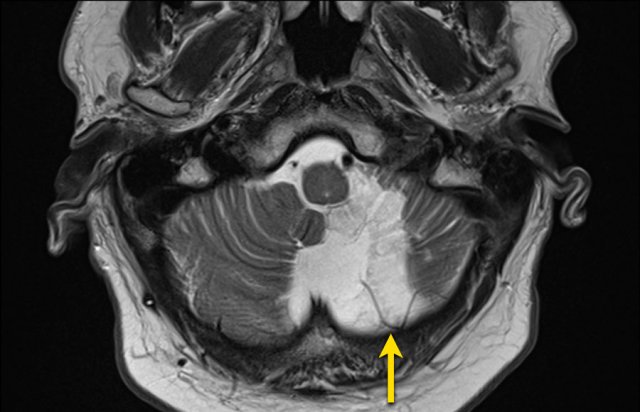

Perimesencephalic SAH

Perimesencephalic subarachnoid hemorrhage (PMSAH) is a subarachnoid hemorrhage with a different etiology and prognosis (ref).

It is centered anteriorly to the pons and midbrain but may extend in small amounts into the basal and suprasellar cisterns and even into the Sylvian and interhemispheric fissure.

Perimesencephalic subarachnoid hemorrhage is a nonaneurysmal form of SAH.

Patients with a perimesencephalic nonaneurysmal subarachnoid hemorrhage are not at risk for rebleeding in the initial years after the hemorrhage and have a normal life expectancy.

The causes of PMSAH suggest a venous or capillary rupture at the level of the tentorial hiatus.

The images show a slightly hyperdense focus in the prepontine and interpedunclair cystern in a patient who presented with acute severe headache.

DSA did not show an aneurysm.

This patient complained of sudden onset headache with the sensation of a “burst” inside his head.

Neurological exam was normal, except for a stiff neck.

The NECT showed a small amount of subarachnoidal blood anterior of the brainstem.

CTA showed no abnormalities.

DSA was not performed.

Here another example of a nonaneurysmal perimesencephalic SAH.

Left image: NECT showed a small amount of subarachnoidal blood anterior to the brainstem.

Right image: more cranially, the pentagon, ambiens cistern and the proximal part of Sylvian’s fissures, did not show any blood.

This is a typical presentation of nonaneurysmal perimesencephalic SAH.

The blood is solely located around the brainstem.